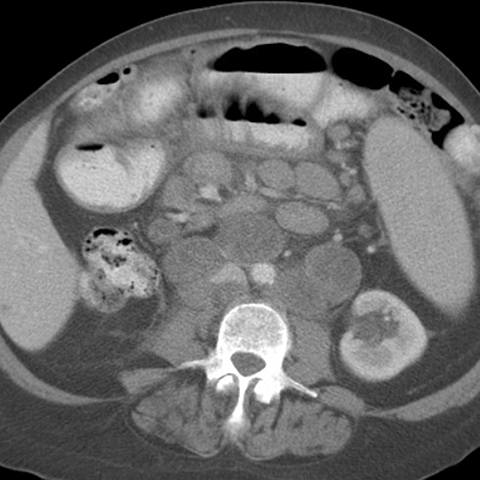

26 year-old male presents with night sweats, weight loss and fever. [2 of 3]